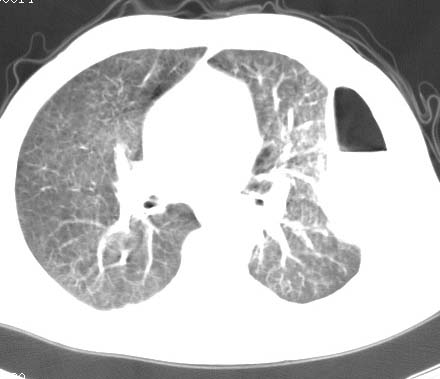

男性 病人 30岁,活动后气促2月余.隔疝伴胸腔积液.右上肺结核!

双肺上结核;膈肌裂孔疝。

左侧胸腔积液,并胸腔内见多个含液 气组织,并相互重叠。影像特征很特殊,应该是“膈疝”。支持!

左侧膈疝,及左侧胸水,双上肺结核。

支持!左侧膈疝,左侧胸水,双上肺结核。

左侧胸腔包裹性液气胸未除。

左膈疝?